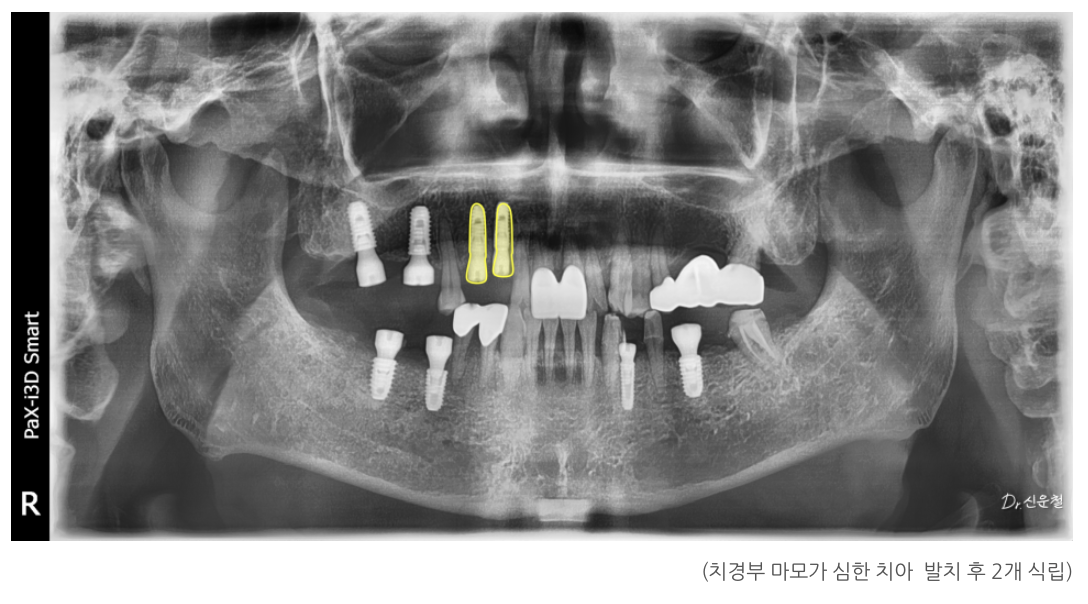

첫 촬영(파노라마·구강 사진)에서 크게 4가지 문제가 확인됐습니다.

① 아래 어금니 상실 → 위 치아 정출(내려옴)

오래전 빠진 아래 어금니 때문에

맞물리는 위 치아가 천천히 아래로 내려오는 정출이 진행되어 있었습니다.

환자분은 총 5개 부위에 임플란트를 먼저 식립했습니다.

3단계: 치경부 마모가 심한 치아는 발치 후 임플란트

해당 치아는 발치 후 임플란트를 진행했습니다.